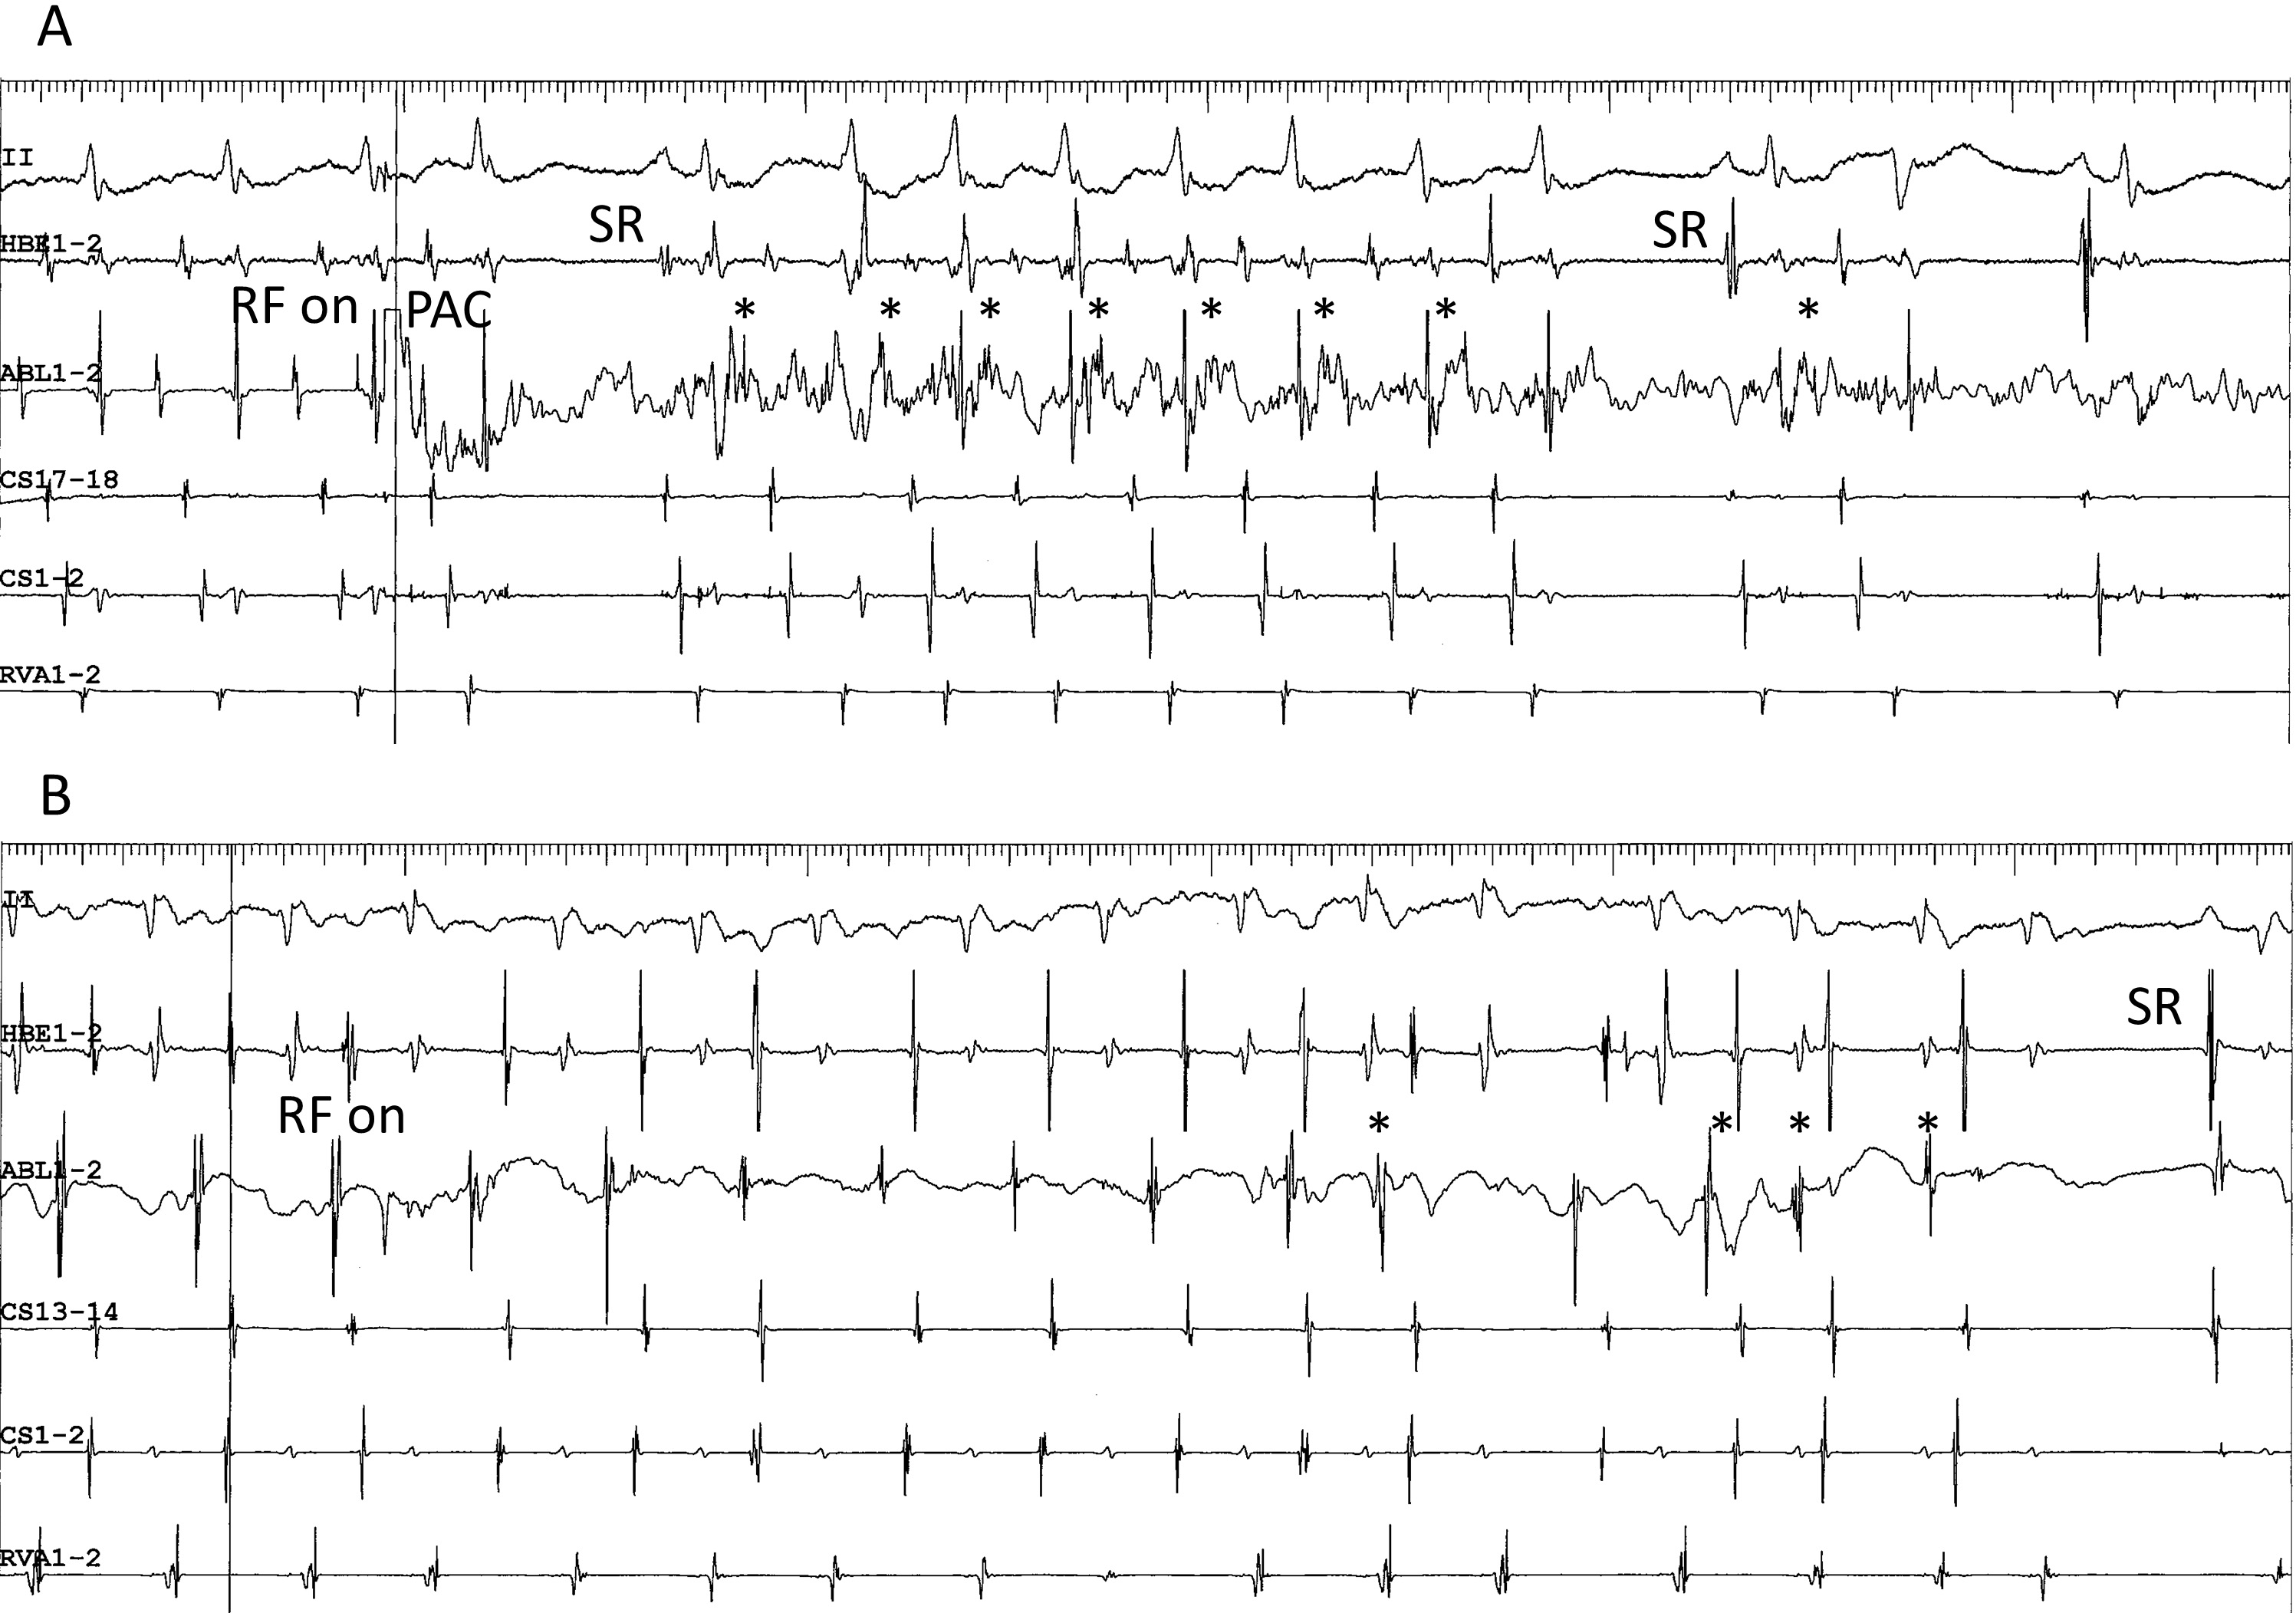

The second characteristic is the detection of low-frequency potentials preceding the local atrial activation, near the site of successful ablation. As described earlier, these potentials are found in the superoanterior or inferolateral fast-slow AVNRT (Fig. 4C,D, respectively) and may reflect retrograde activation across the SP [58]. Although the presence of prepotentials during adenosine-sensitive atrial tachycardia has not been reported previously [67, 80, 85], we have reproducibly detected low-frequency prepotentials within a localized area near the site of earliest atrial activation during an atrial tachycardia originating from the inferolateral right atrium, along the tricuspid annulus (Fig. 4E). Yamabe et al. [86] have described low-frequency, late potentials following local atrial activation during sinus rhythm, probably reflecting a delayed activation of the tachycardia origin, near the site of successful ablation, in patients presenting with atrial tachycardia originating from the tricuspid annulus. The presence of these potentials suggests a slowly conducting, common arrhythmogenic substrate of these tachycardias. The third characteristic is the development of accelerated atrial ectopic activity during delivery of radiofrequency energy. This is often observed during ablation of right atrial, superior, superoanterior (Fig. 7A) and inferolateral SP, as described earlier. Moreover, in contrast to previous reports [80, 86], we have also observed it during ablation of atrial tachycardia originating from the tricuspid annulus (Fig. 7B). This activity may be caused by heating of the AV nodal transitional cells present in these tissues [63]. The fourth characteristic is the occurrence of multiple shifts of the site of earliest atrial activation during tachycardia with each radiofrequency application. As described earlier, this phenomenon is occasionally observed after the ablation of superoanterior or inferolateral right atrial SP, or of atrial tachycardia originating from the tricuspid annulus [69]. Collectively, these anatomical, electrophysiological and pharmacological characteristics suggest that the AV node-like tissue distributed around the tricuspid annulus is the arrhythmogenic substrate shared by these tachycardias.

Fig. 7.Development of accelerated ectopic atrial cycles during radiofrequency delivery. (A) Accelerated ectopic atrial rhythm (asterisks) developing immediately after radiofrequency energy was delivered (RF on) during an ongoing superoanterior-type of fast-slow AVNRT, in the same patient as shown in Fig. 4C. The tachycardia is terminated by a premature atrial complex (PAC) immediately after the delivery of radiofrequency energy. (B) ATP-sensitive atrial tachycardia originating from the inferolateral right atrium along the tricuspid annulus, followed by return to sinus rhythm (SR) in the same patient as in Fig. 4E. II, surface electrocardiogram lead II; HRA1-2, high right atrium; HBE1-2, His bundle electrogram; CS13-14 to 1-2, proximal to distal coronary sinus; RVA1-2, right ventricular apex.

We observed the noteworthy case of a 68-year-old man who developed ATP-sensitive atrial tachycardia late after ablation of a superoanterior SP mediating a superoanterior-type of fast-slow AVNRT (Figs. 4C,8). The 12-lead electrocardiogram during tachycardia revealed the presence of a long RP interval, with a biphasic P wave in the inferior leads (Fig. 4C). The tachycardia was induced with ventricular stimulation following a dual atrial response (Fig. 8A) [30]. Fast-slow AVNRT was diagnosed after the exclusion of AV reentry by the observation of VA dissociation during ventricular overdrive pacing of the tachycardia, which required 12 mg of ATP for its termination. Electroanatomical activation mapping of the right atrium during ongoing tachycardia revealed a site of earliest atrial activation in the superoanterior right atrium along the tricuspid annulus (Fig. 4C). The successful ablation of the tachycardia by delivery of radiofrequency energy at or near that site (Fig. 4C) was followed by a brief run of accelerated ectopic atrial rhythm (Fig. 7A). The long RP tachycardia recurred six months later, with a P wave morphology and polarity, and site of earliest atrial activation like those observed before the ablation procedure. However, in contrast to the fast-slow AVNRT present before ablation, ventricular entrainment pacing of the tachycardia revealed the presence of intraatrial fusion (Fig. 8B), confirming the diagnosis of atrial tachycardia [87]. Moreover, the dose of ATP required to terminate the recurrent tachycardia had decreased to 2.0 mg, suggesting a change in the electrophysiological properties of the substrate. A successful second ablation procedure was performed at or near the site of earliest atrial activation. In this case, we hypothesize that the common, ATP-sensitive, arrhythmogenic tissue was the superoanterior SP and origin of the atrial tachycardia, and that the latter might be an atrial remnant of SP isolated by the ablation.

Fig. 8.Example of superoanterior type fast-slow AVNRT (A) followed by the development of atrial tachycardia (B) originating from the superoanterior right atrium, along the tricuspid annulus, after ablation of a superoanterior SP. This is the same patient as in Fig. 4C. (A) Induction of superior-type of fast-slow AVNRT by ventricular overdrive pacing at an S-S cycle length of 670 ms. Retrograde conduction via a FP is present after the 1st and 2nd stimuli, with an earliest site of atrial activation in the His bundle region (HBE1-2). Immediately after the 2nd stimulus, a long RP tachycardia with a site of earliest atrial activation in the high right atrium (HRA1-2) is induced, after a V-A-A-V response where the 367-ms interatrial interval is 88 ms shorter than the 455-ms tachycardia cycle length, consistent with a dual atrial response from simultaneous retrograde conduction (dotted arrows) over the FP and the superoanterior SP. The 3rd and 4th stimuli (S), do not capture the ventricles. (B) Ventricular entrainment pacing at an S-S cycle length of 320 ms during ongoing atrial tachycardia with a site of earliest atrial activation in the HRA. Ventricular overdrive pacing captures the atrial electrogram via the FP in HBE1-2 (dotted arrows) after the 3rd stimulus, without capture of the atrial electrogram in HRA1-2, suggesting intraatrial fusion of a retrograde wavefront originating from the FP, with an atrial wavefront propagating from the site of origin of the atrial tachycardia. II, surface electrocardiogram lead II; HRA1-2, high right atrium; HBE1-2, His bundle electrogram; CS7-8 to 1-2, proximal to distal coronary sinus; RVA1-2, right ventricular apex.